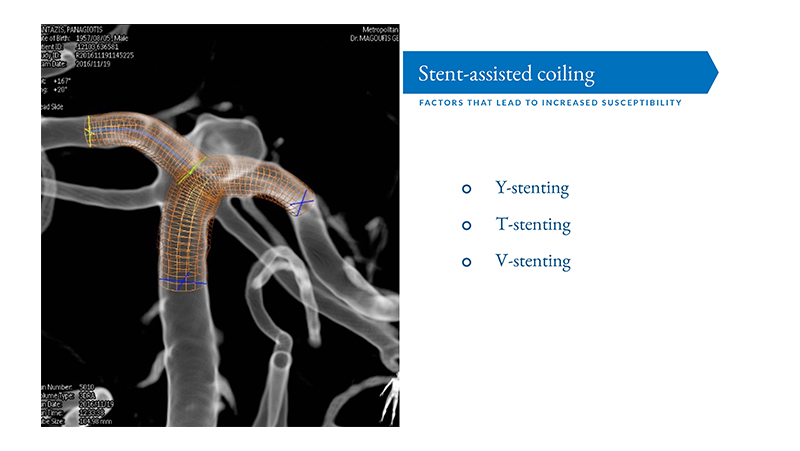

Εικόνα 2: Στην προκειμένη περίπτωση, λόγω της μορφολογίας του αυχένος, θα χρησιμοποιηθεί η τεχνική του Y-stenting όπως φαίνεται στην παραστάση virtual stenting του αγγειογραφικού μηχανήματος.